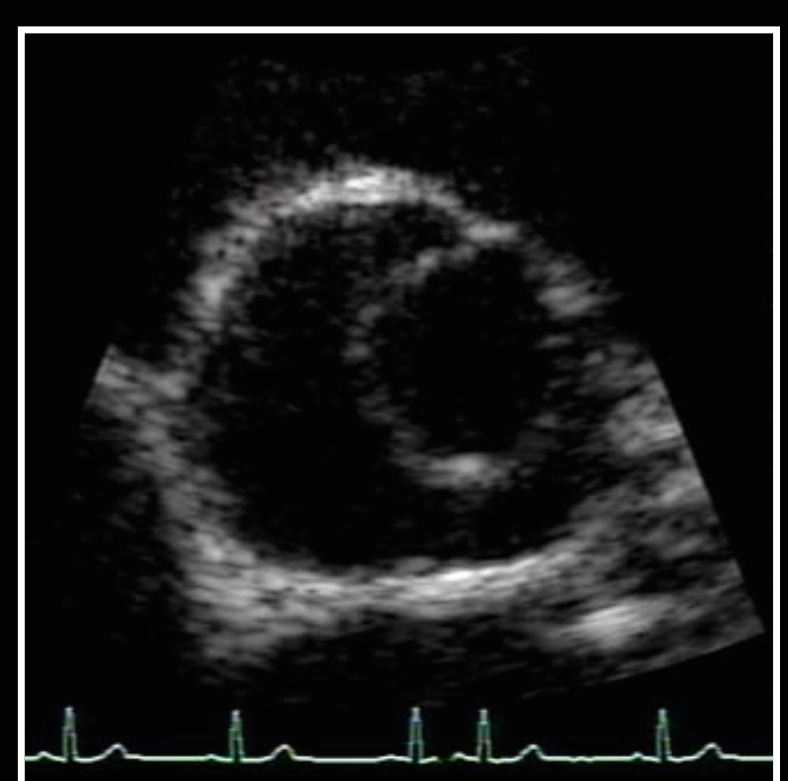

Diagnosis?

Unicuspid AV